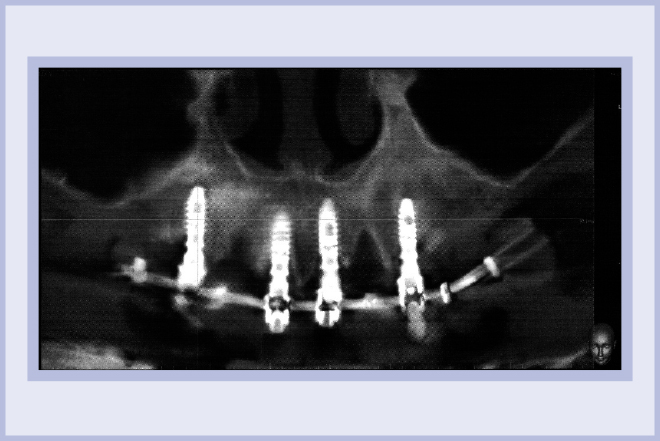

Si è presentata presso il nostro studio una paziente di 73 anni portatrice di una protesi mista (fissa e mobile) nel mascellare superiore (Fig. 1). Si è pianificata una riabilitazione immediata dell’intera arcata mediante tecnica tipo All-on-Four.

- Fig. 13 – Immagine radiografica di controllo al termine dell’intervento